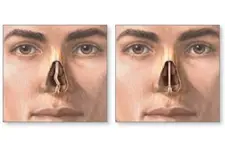

Burun Kıkırdak Eğriliği Belirtileri ve Tedavisi Burun kıkırdak eğriliği, burun septumunun (burun ortasındaki yapı) anormal bir şekilde eğrilmesi veya şekil bozukluğu olarak tanımlanabilir. Bu durum, bireylerin yaşam kalitesini etkileyen ve çeşitli sağlık sorunlarına yol açabilen önemli bir rahatsızlıktır. Burun kıkırdak eğriliği, genellikle doğuştan gelir, ancak travma veya yaralanmalar sonucu da gelişebilir. Burun Kıkırdak Eğriliğinin Belirtileri Burun kıkırdak eğriliği, birçok belirtiyle kendini gösterebilir. Bu belirtiler kişiden kişiye değişebilir, ancak genel olarak aşağıdaki semptomlar sıklıkla görülmektedir:

Bu belirtiler, bireyin günlük yaşamını olumsuz etkileyebilir ve bazen daha ciddi sağlık sorunlarına yol açabilir. Burun Kıkırdak Eğriliğinin Nedenleri Burun kıkırdak eğriliğinin nedenleri genellikle aşağıdaki gibi sıralanabilir:

Sonuç Burun kıkırdak eğriliği, birçok bireyi etkileyen yaygın bir durumdur. Belirtiler, yaşam kalitesini olumsuz etkileyebilir ve tedavi edilmediği takdirde daha ciddi sorunlara yol açabilir. Bu nedenle, burun kıkırdak eğriliği belirtileri yaşayan kişilerin bir uzmana başvurması önemlidir. Tedavi seçenekleri sayesinde, bireyler bu rahatsızlıktan kurtulabilir ve daha sağlıklı bir yaşam sürdürebilirler. Ek olarak, burun kıkırdak eğriliği ile ilgili daha fazla bilgi edinmek isteyen bireylerin, kulak burun boğaz uzmanları ile iletişime geçmeleri önerilmektedir. Bu uzmanlar, durumun ciddiyetini değerlendirerek en uygun tedavi yöntemini belirlemede yardımcı olabilirler. |